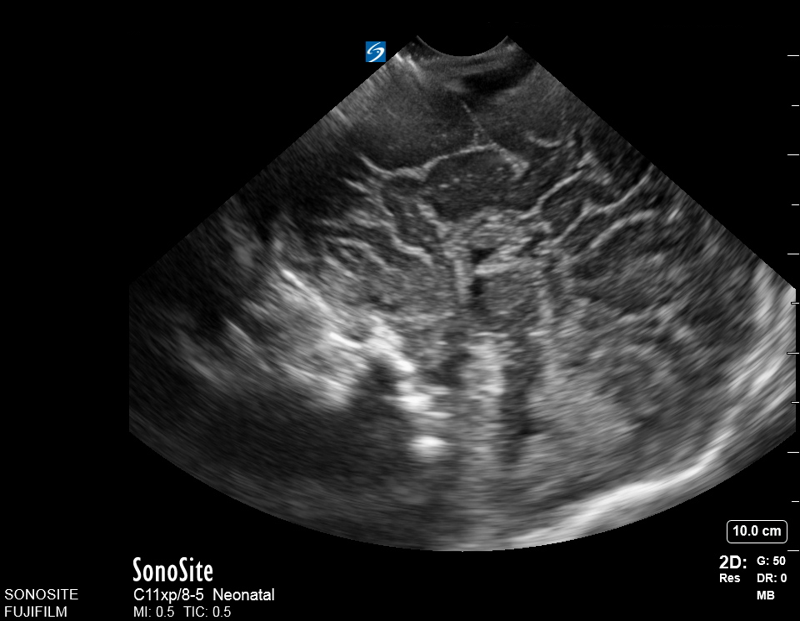

Neonatology Corpus Callosum Agenesis 1 Image